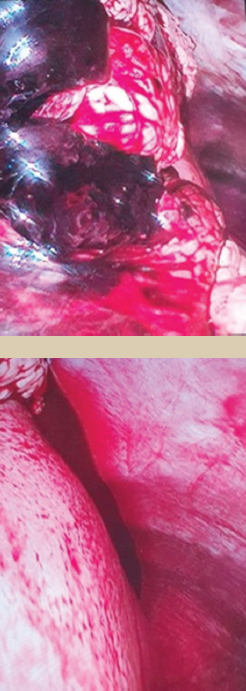

Ante estos hallazgos, se decidió realizar cirugía laparoscópica programada, en la que se identificó hemoperitoneo (figura 4), motivo por el cual se cambió a cirugía abierta, donde se visualizaron 2 vasos sangrantes del mesenterio, que fueron reparados.

Imagen: Argüello Ramírez et al.

Figura 4 Hematoma coagulado con abundante sangre en cavidad peritoneal.

En nuestro caso, el paciente acudió por dolor abdominal difuso asociado a pérdida de peso, por lo que inicialmente se pensó en una patología neoplásica. Se decidió realizar el procedimiento quirúrgico por vía laparoscópica, donde se confirmó el hematoma, motivo por el cual se convirtió a cirugía abierta, en la que se visualizó el origen del sangrado a nivel de los vasos mesentéricos, los cuales fueron reparados satisfactoriamente sin complicaciones postquirúrgicas.